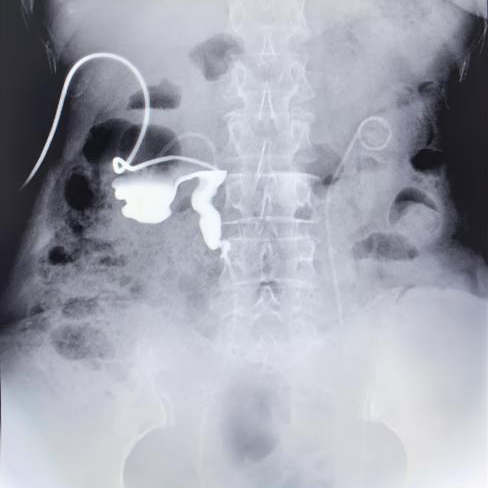

术前影像检查清晰显示患者双侧肾积水及输尿管受压

入院完善相关检查后,医师发现患者右侧输尿管受到肿瘤严重压迫,其承担主要排毒功能的肾脏产生的尿液完全无法流入膀胱。针对这一棘手情况,赵洪青、周骥带领团队经过审慎评估,最终为患者确定了“黑科技”金属温控输尿管支架置入术这一精准治疗方案。